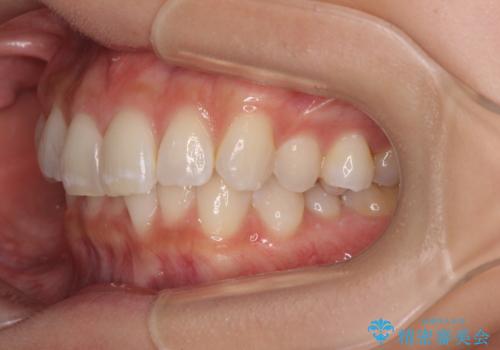

デコボコの非抜歯矯正 ワイヤー装置で楽して改善

- 上下前歯のデコボコとディープバイトを気にして来院された患者様です。

歯列全体に叢生があり、舌の突出癖が認められたため、突出癖が改善されない場合には口元が突出するリスクが考えられました。

マウスピースでもワイヤーでも対応可能でしたが、煩わしいことは避けたいとのことで、舌のトレーニングをしっかりと行っていただきながら、ワイヤー装置にて矯正治療を行うこととしました。